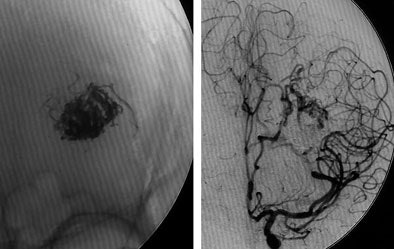

| Digital subtraction angiography shows arteriovenous malformation at presentation (top, below) and two weeks postembolization (bottom) with endovascular administration of ethylene vinyl alcohol copolymer embolization agent (Onyx, Micro Therapeutics, Irvine, CA). The patient had repetitive transient ischemia attacks due to cerebral steal from the AVM. Images courtesy of Dr. Michael Forsting. |

In another example, a patient with an AVM located in the speech center of the patient's brain was a "No-touch AVM" for the neurosurgeon if not the endovascular therapist, according to Forsting. "We know these are pretty dangerous," he said. "Nowadays we go in with a catheter and we can occlude them completely." Late-venous-phase CT three weeks later showed complete occlusion, and the patient suffered no neurologic deficit.

The risk of surgery is largely dependent on the size of the AVM, Forsting said. A large AVM brings a 50% risk, which is reduced tenfold for smaller AVMs.

"Endovascular therapy is mandatory in all patients with AVM, and you need to treat all patients with AVM," he said. A 2002 study by Simon et al examined the long-term outcomes of patients with intrinsic brain AVM. Over an average 10 years of follow-up, conservative management produced a 24.6% mortality rate, while active management reduced mortality and morbidity to 3.9% (p = 0.031), Forsting said (Stroke, December 2002, Vol. 33, pp. 2794).